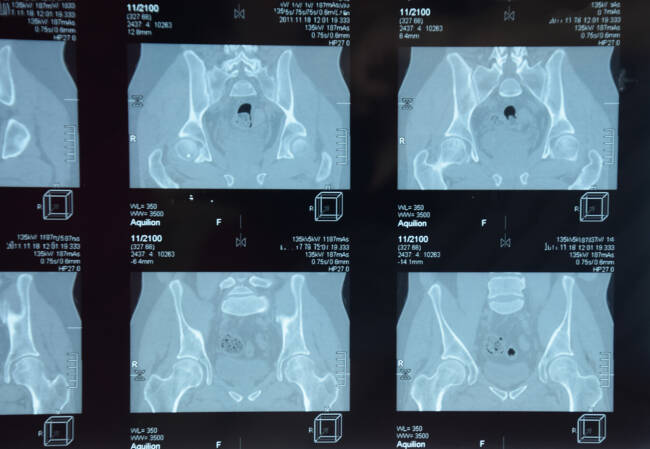

I studien, som ble presentert på forskningskongressen EULAR i 2021, ønsket forskerne å undersøke dette SpA-trekket hos de som hadde en bekreftet nr-axSpA-diagnose. De ville også vurdere sammenhengen mellom endringene i symfysen og andre kliniske trekk ved sykdommen. De hadde 40 pasienter, hvor to forskjellige revmatologer hadde konstatert radiologiske endringer i skambensymfysen ved hjelp av røntgen av bekkenet. Det ble også registrert inn resultater fra tidligere røntgen- og MR-undersøkelser når det gjaldt betennelse og endringer i iliosakralleddene (IS-ledd) i bekkenet.

Endringene i symfysen ble delt inn i fem kategorier, der grad 4 var ankylose, som betyr at det forekom leddstivhet på grunn av sammenvoksing av leddender. Ved grad 3 forelå det markert sklerose, med hardt, fast og fortykket vev på grunn av økt bindevevsdannelse eller kalkavleiringer. Ved grad 2 ble det vurdert å være en subtil uregelmessighet og/eller en fortykkelse av beinet i leddet. Ved grad 0 ble leddet vurdert til å være normalt.

Forskerne avdekket radiografiske endringer i symfysen hos 37,5 prosent, altså 15 pasienter. Ti av dem ble klassifisert til å være i grad 2, mens tre til grad 3. Kun en ble avdekket med endringer tilsvarende gradene 0 og 4.